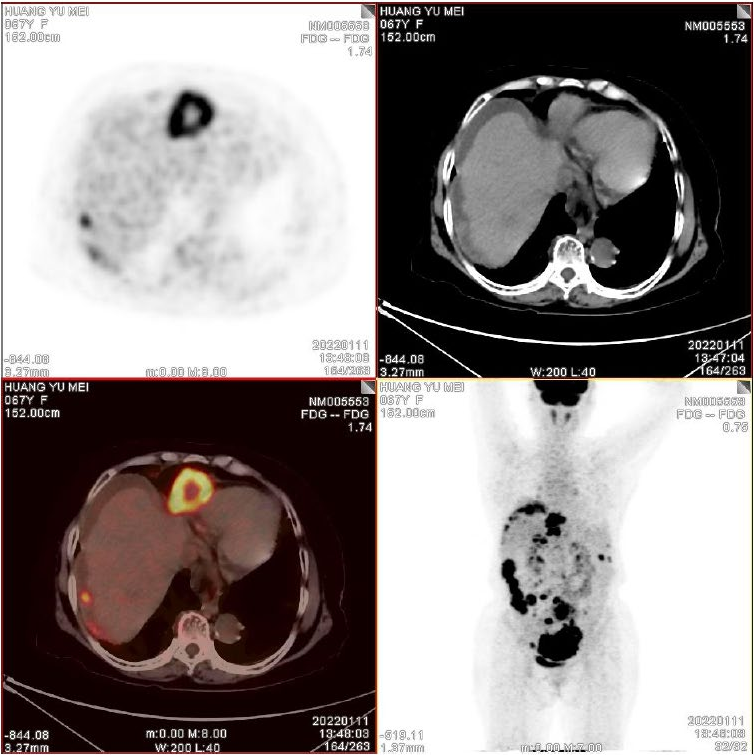

患者,67岁

• 腹胀1+月

• B超发现盆腔肿物

• PET:如下图诊断报告所示

• CA125:1025 IU/L

• Suidan评分:6分